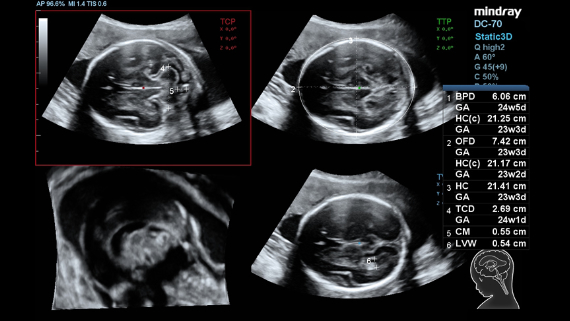

Imagens clĂnicas